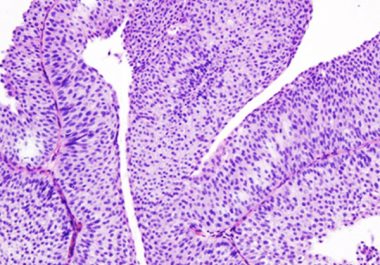

The FDA has approved the FGFR inhibitor erdafitinib for certain patients with urothelial carcinoma The U.S. Food and Drug Administration (FDA) has approved erdafitinib (Balversa) for the treatment of adult patients with locally advanced...